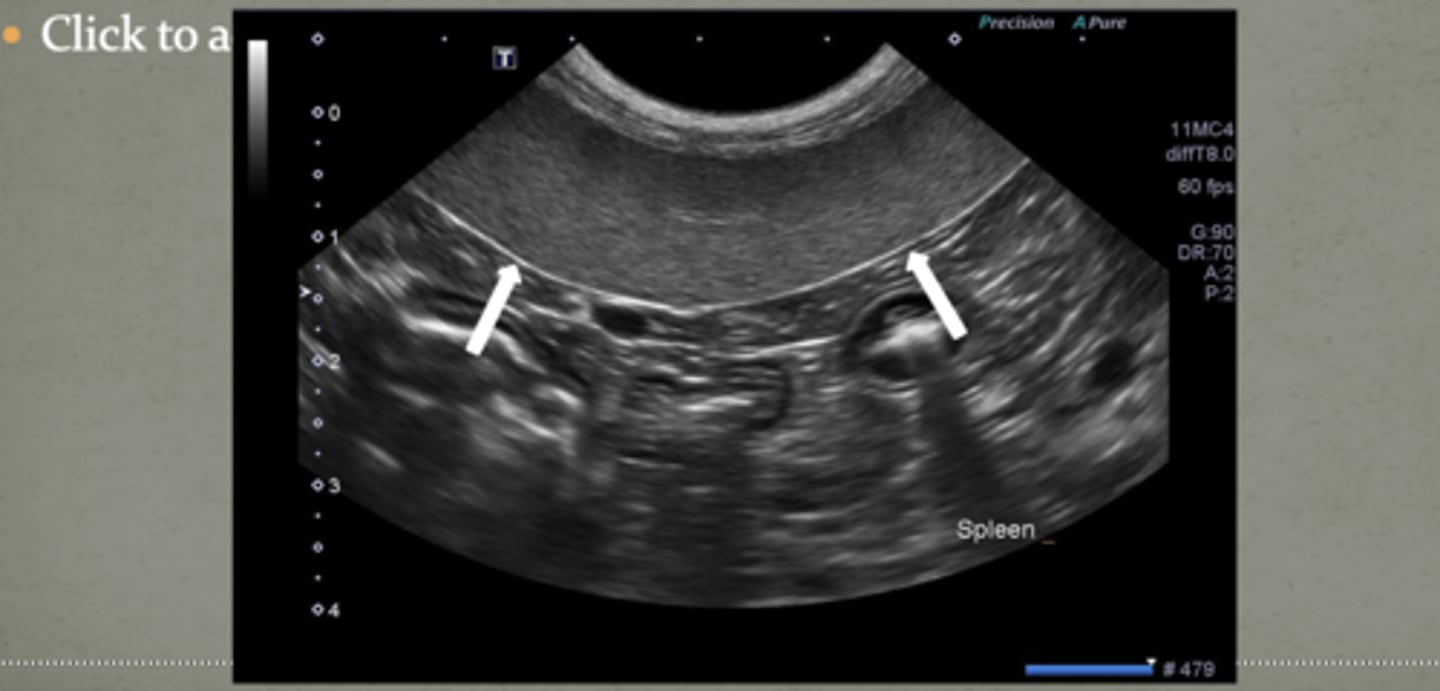

this is the spleen, just know what it looks like!!

well-defined

in normal US of the spleen, the capsule is usually ________

-homogenous

-less coarse

the spleen has ______ parenchyma with uniform finely stippled pattern less/more coarse than the liver

liver and renal cortex

the spleen is more hypoechoic than what two structures in the dog?

isoechoic or hypoechoic

in cats, the spleen can be _________ or ________ to the renal cortex (echogenicity-wise)

smooth

it is important to look for _______ borders of the spleen to detect masses